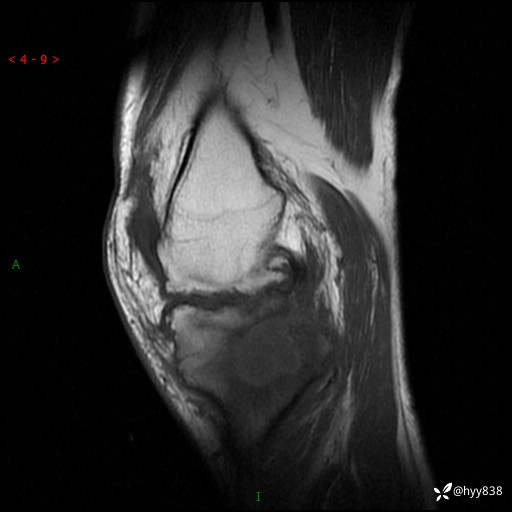

MRI(sag :T1WI+T2WIfs)